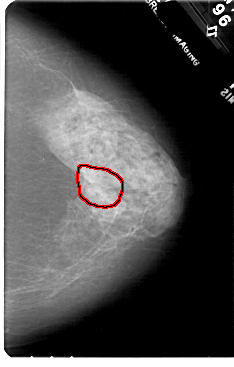

FILE: A_1720_1.LEFT_MLO.OVERLAY

TOTAL_ABNORMALITIES 1

ABNORMALITY 1

LESION_TYPE MASS SHAPE ARCHITECTURAL_DISTORTION MARGINS SPICULATED

ASSESSMENT 2

SUBTLETY 5

PATHOLOGY BENIGN_WITHOUT_CALLBACK

TOTAL_OUTLINES 1

BOUNDARY